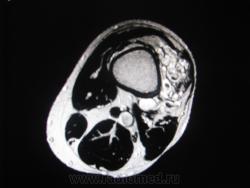

МРТ мягких тканей нижней трети левого бедра мужчна 46 лет.

Много лет беспокоит припухлость в задне-наружных отделах нижней трети левого бера, в последннее время выраженный болевой с-м, с диагнозом хронический гематогенный остеомиелит направлен на МРТ.При осмотре пальпируется образование вышеуказанных отделов, кожные покровы интактны.

Я бы заподозрил гемангиому с необходимостью дифференциальной диагностики с гемангиоперицитомой.

Остеомиелит - почему?? Кость, насколько можно судить по представленным изображениям, вообще интактна. Мы видим в мягких тканях образование "петлистой" структуры, скаладывается впечатление, что имеется его связь с сосудами. Смахивает на гемангиому. Исследование с контрастным усилением не делали?

Совершенного верно , это гемангиома. А почему остеомиелит,  для меня тоже загадка. Пациент что-то толковал насчет неровгогго контура кости на ренгене ( с собой не принес), может, на фоне этой штуки действительно неотчетливо визуализировалась кость? Хотя кроме лучевой картины для остемиелита есть масса других с-мов! Контрастировали, представлен один постконтрастный корональный  скан( последний  кадр) .Я думаю, здесь нужна селективная ангиография, для детального выявления питающего и дренирующего сосуда и работа ангиохирургов.